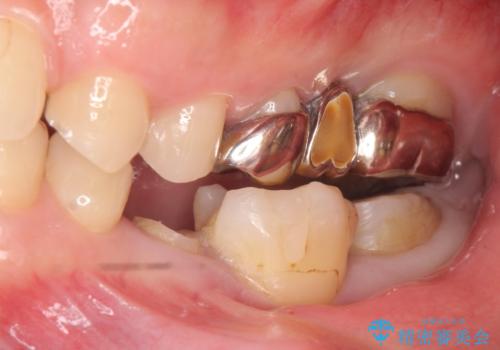

- 左下の奥歯がズキズキ痛むので診て欲しいといらっしゃった方の症例です。他院では5番目と7番目の歯を抜歯してインプラントと言われたが、出来れば歯を残したいとのことでした。

痛みの原因は6番目の虫歯であること、5番目、6番目の歯は歯茎より深い虫歯であり現状では保存が難しいことを説明した上で、歯を挺出させる部分矯正と歯茎を下げる歯周外科を行いました。